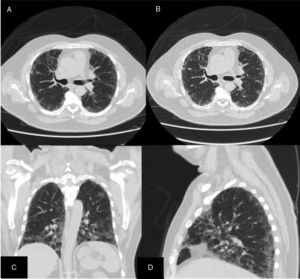

ResultsWe could include 230 patients (female 177 (77%) and males 53 (23%)) with established RA, fulfilling the 2010 ACR/EULAR classification criteria for RA.12 Their mean age was 47.06±11.75 years and disease duration 64.11±54.72 months. RF was positive in 101 (43.9%) and ACPA was positive in 220 (95.7%), while ANA was positive in 58 (25.2%), anti-Ro/SSA in 31 (13.5%), anti-La/SSB in 10 (4.3%), anti-RNP in 2 (.9%) and none of the patients showed anti-Sm antibodies. Anti-Jo-1 was positive in 5 (2.2%), none of them had increased CPK levels and all five cases showed typical erosive changes consistent with the diagnosis of RA (Fig. 1). Two out of the 5 cases with positive Anti-Jo-1 had ILD (Figs. 2 and 3). Detailed demographic features, clinical manifestations, laboratory investigations, SHS, drug therapy and disease activity scores are summarized in Table 1. In the controls (n=75), RF (low titer) was positive in 4, ANA was positive in two (2.7%), anti-Ro/SSA in three (4%), and none of the control group tested positive for anti-La/SSB, anti-Sm, anti-Jo-1, anti- U1RNP autoantibodies and none tested positive for ACPA.

An interesting finding in our study is the positive anti-Jo-1 in five (2.2%) patients, and two of them had aggressive ILD who can be classified as RA-ASS overlapping syndrome. Anti-Jo-1 correlated positively with ILD and RF titer. One patient had a high RF titer, negative ACPA and positive ANA, erosions typical for RA, positiveanti-Jo-1, while the other case was seropositive for RF, ACPA and ANA, typical erosions consistent with the diagnosis of RA and concomitant ILD and we classified the two cases with ILD as having RA-ASS overlap. Methotrexate (MTX) induced hypersensitivity pneumonitis cannot explain acute respiratory distress syndrome as observed in two of our patients with RA-ASS overlapping syndrome. First MTX induced hypersensitivity pneumonitis usually occurs in the initial weeks to months of starting treatment with MTX as acute drug reaction33; second no significant association was observed between MTX dose and ILD in our study (p=.701); third and most important it is not known that MTX can induce positive anti-Jo-1 autoantibodies which are now considered the hallmark diagnostic autoantibody in ASS.